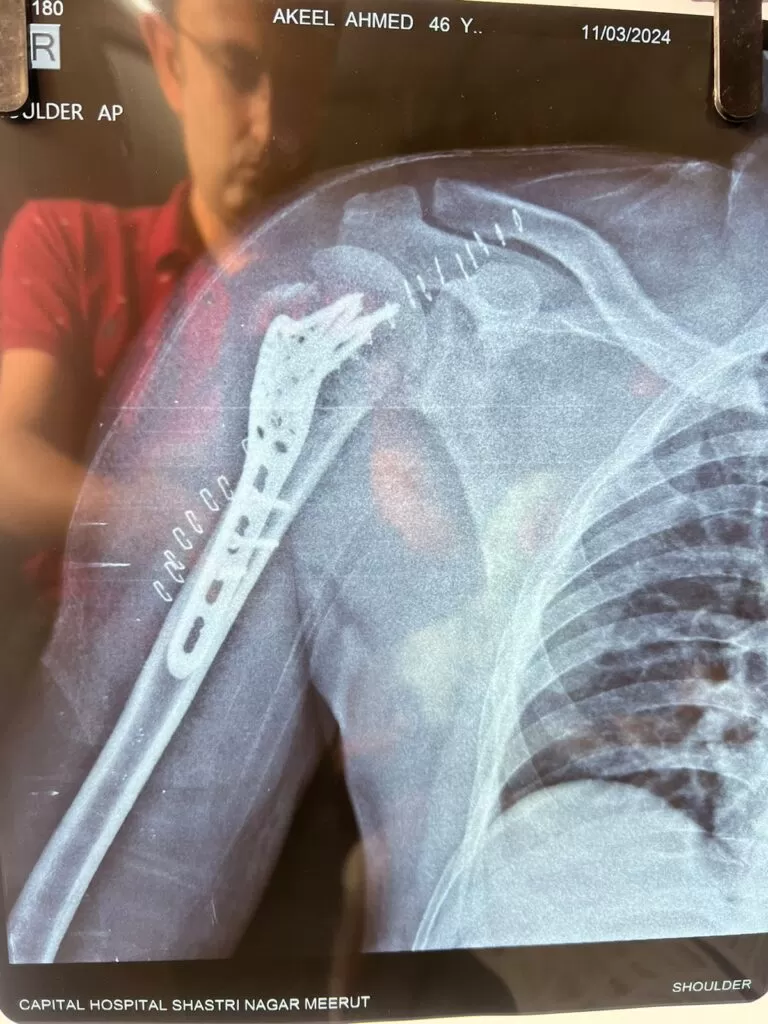

Mr. Akeel

Name: Mr. Akeel

Date of Operation: 10 Mar 2024

Age: 46 Years

Complex Trauma